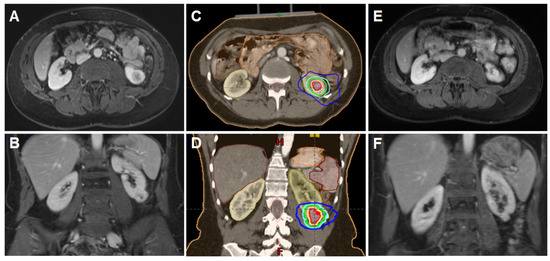

2.3. Immobilization, Planning and Delivery of Stereotactic Body Radiotherapy